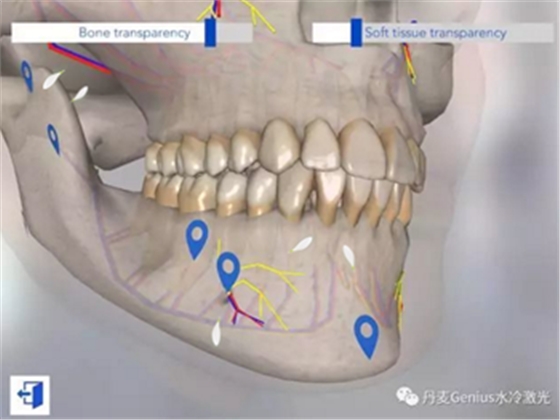

上頜表麻的注射位點

下頜表麻的注射位點

以上視頻來自加拿大的哥倫比亞學(xué)院的牙科分校的教學(xué)視頻。如果還是覺得困難,也可以在iPad上下載一個牙科麻醉注射的AR模擬器,慢慢找位置。第三行,第一列。

【牙科洽談iPad】/【3D實時模型】分類